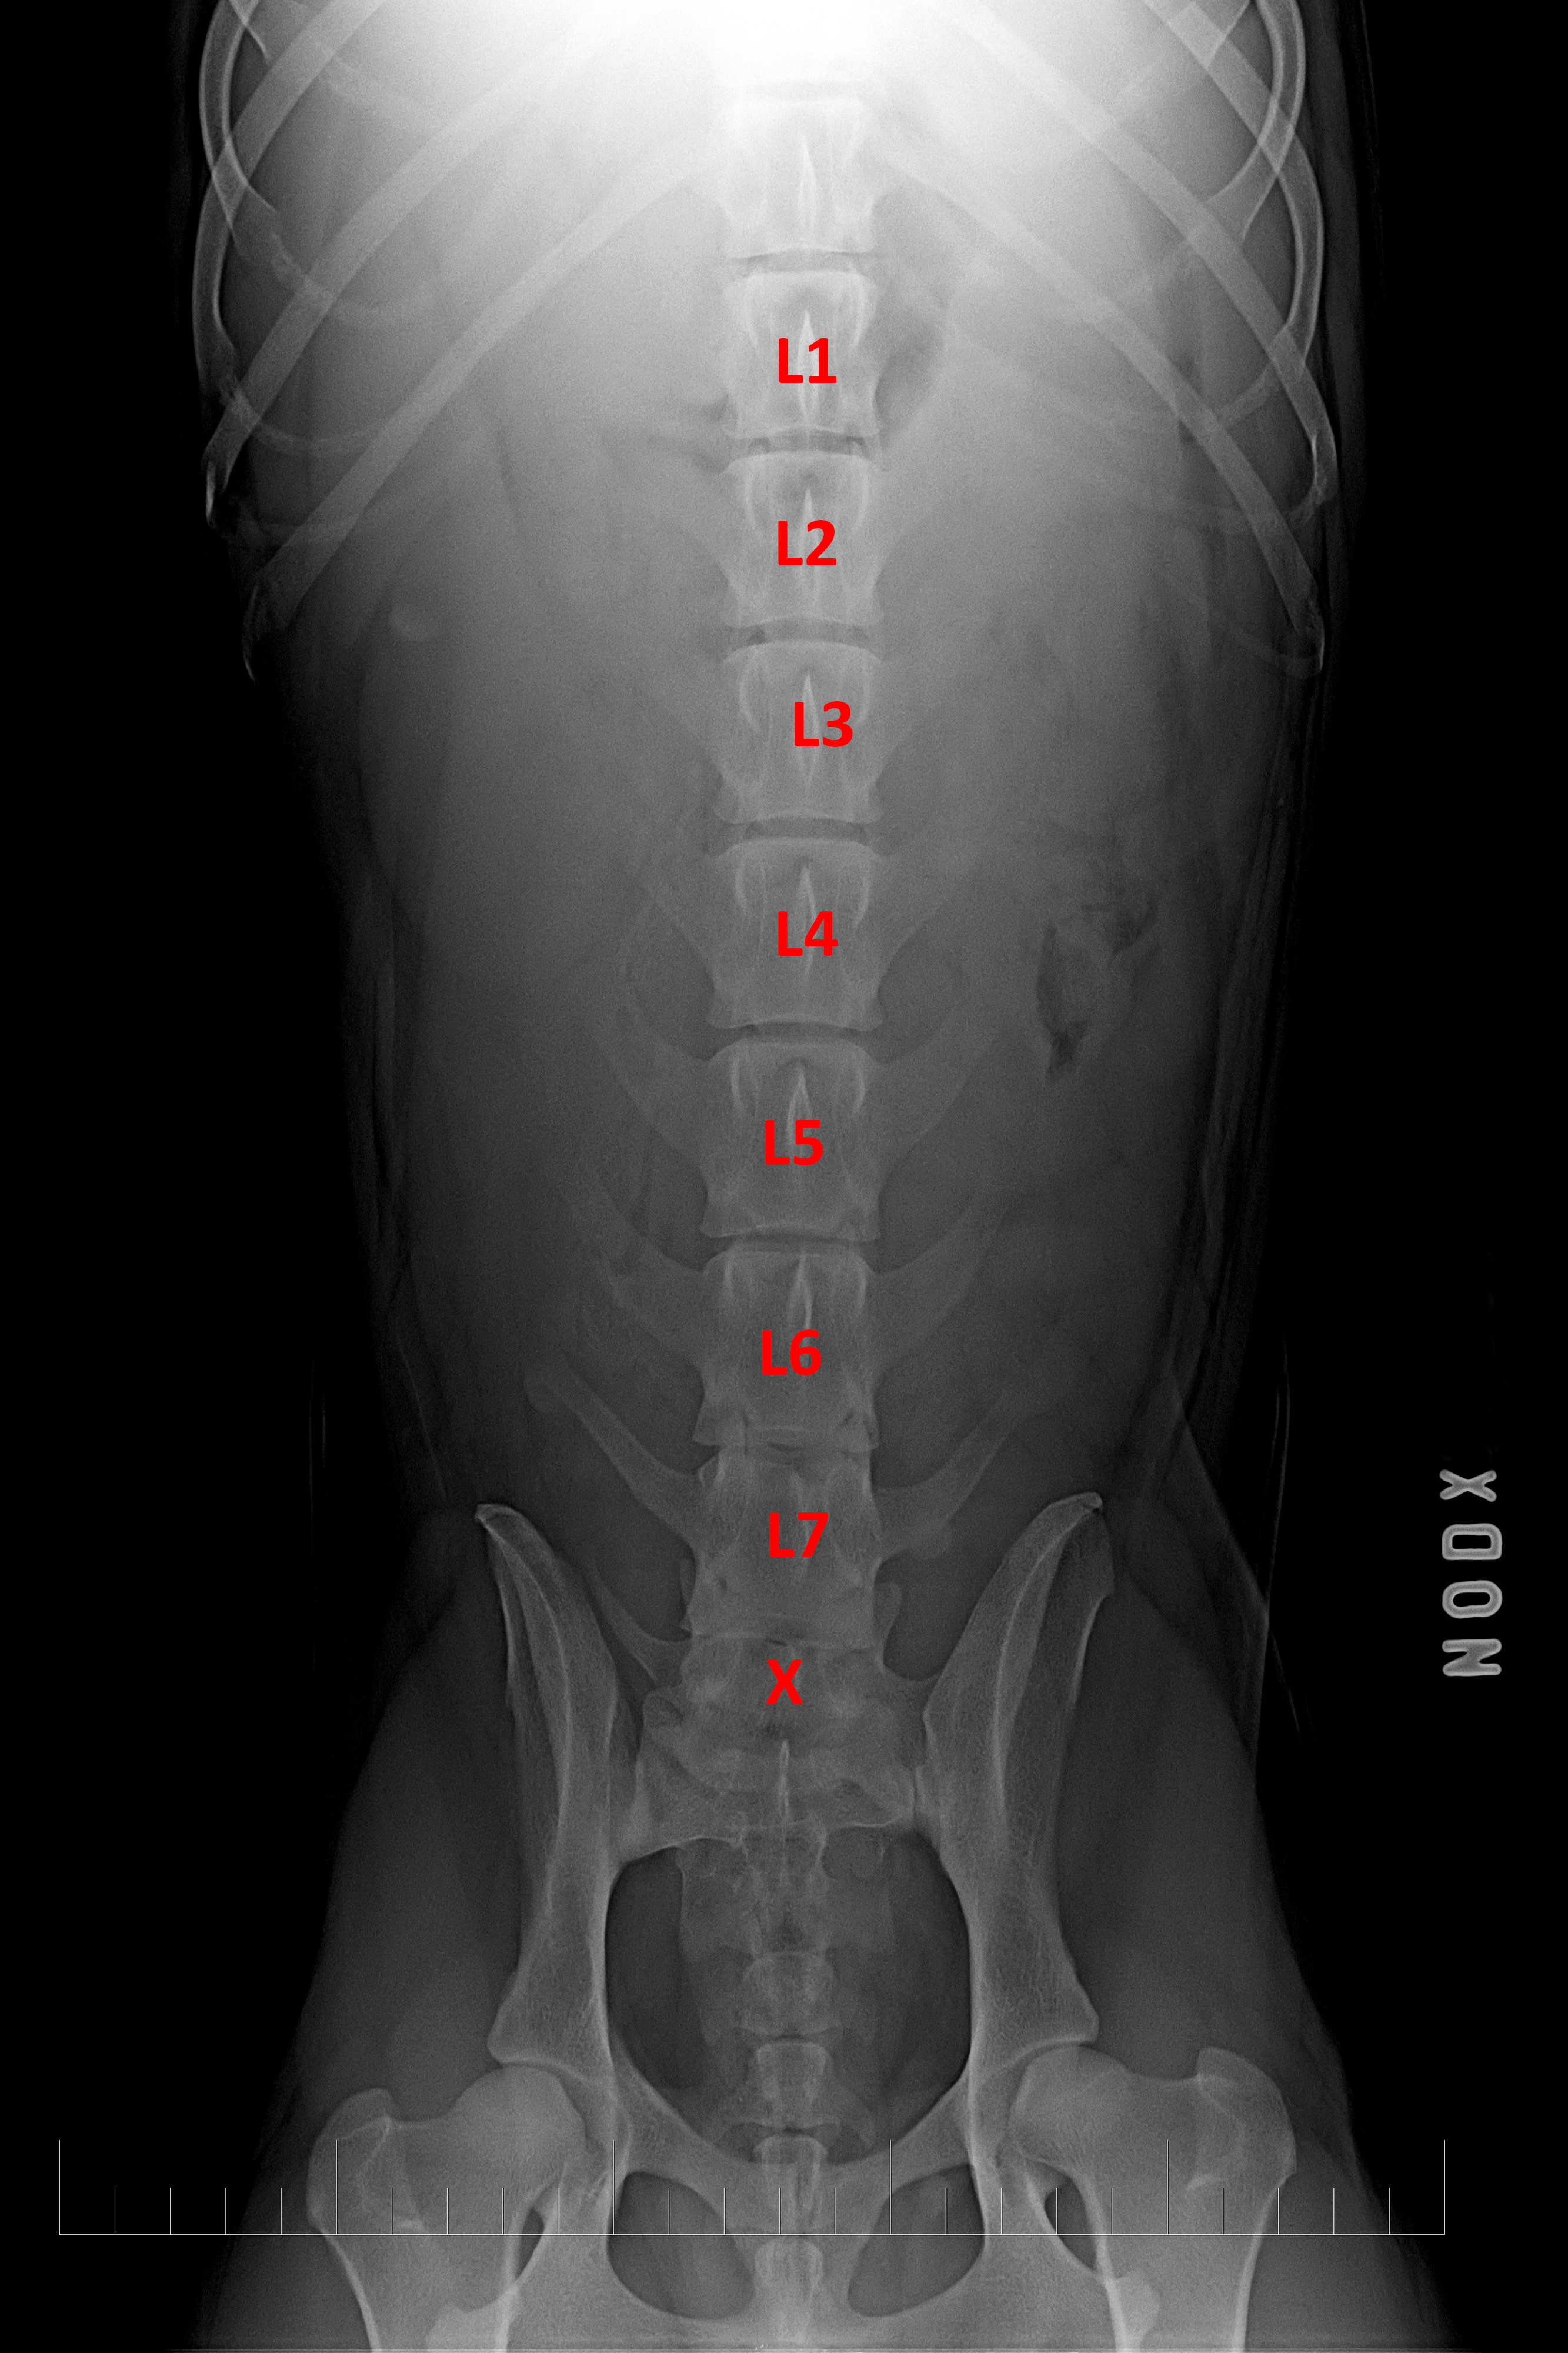

(5) typ 3 páteř VD

páteř psa a možné lokalizace přechodového obratle